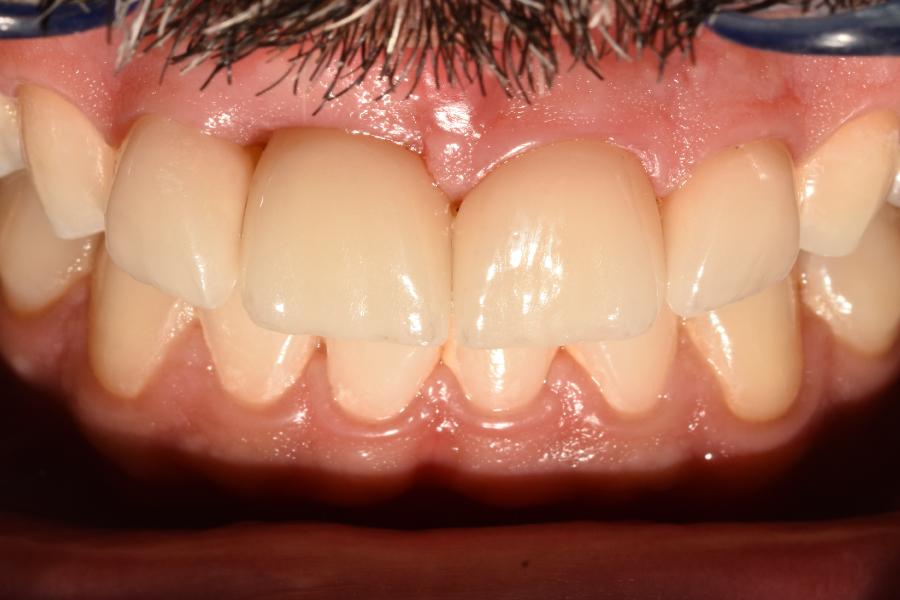

Figura 40

Figura 41

Figura 42

Figura 43

Figura 44

Figura 45

Figura 46

Figura 47

Figura 48

Figura 49